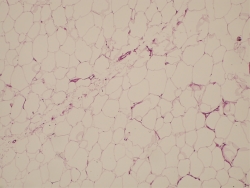

Para realizar un correcto tratamiento es necesario identificar la etiología y, solo en caso de no tener un diagnóstico de certeza, vamos a reconocer la artrofibrosis como causa de la rigidez, como un proceso de metaplasia del fibrocartílago con incremento de la fibrosis intersticial(13)(14)(Figuras 2 y 3). La historia clínica ayuda a pensar en los problemas de cicatrización, la presencia de infección superficial en el postoperatorio inmediato, los traumatismos y en la aparición de una rigidez(15)(16). Un cuadro que aparece en el postoperatorio inmediato lleva a pensar que se trata de un error quirúrgico o una rehabilitación inadecuada, mientras que en el caso de una rigidez de aparición tardía, tras un periodo de movilidad satisfactoria, nos encaminará a un proceso de infección latente o descementación.

Figura 3. Patrón de fibrosis intersticial del paquete adiposo de Hoffa en rodilla rígida.